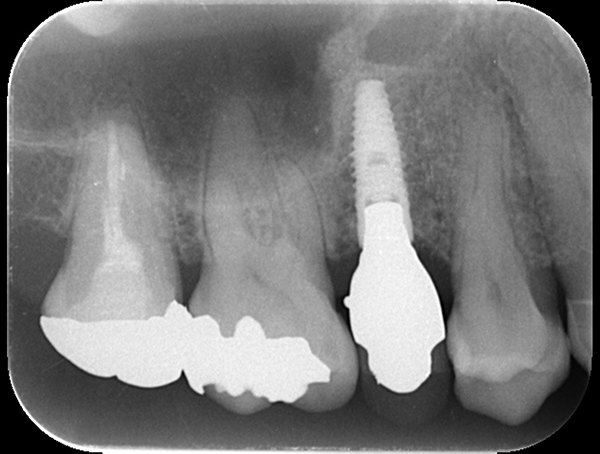

6ヶ月後再び歯茎を切り中の状態を確認。骨がしっかりできており、インプラント手術を行えることが分かると思う。 インプラントを埋めるための穴をあけて、インプラントを埋入した。

麻布十番歯科のインプラント手術の症例

インプラントが2本入っているが左右でインプラント体の種類が異なります。

麻布十番歯科の左右で異なるインプラント体を使用したレントゲン写真